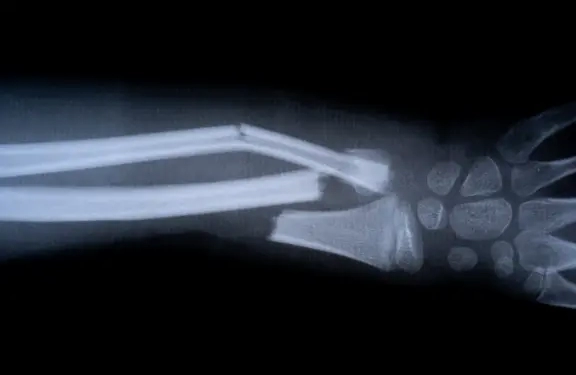

El desarrollo de Bone-02 parte de la observación de cómo las ostras se adhieren con fuerza a superficies en entornos húmedos. Replicando este mecanismo, los investigadores lograron crear un material capaz de fijar fragmentos óseos con seguridad dentro del cuerpo humano.

Bone-02 se aplica mediante una inyección directa en la fractura, donde se solidifica en pocos minutos y comienza a integrarse de manera natural con el hueso. Al ser biodegradable, se degrada progresivamente en el organismo sin necesidad de cirugía posterior.

En estudios preclínicos realizados en animales, Bone-02 demostró una fijación firme y segura, logrando que los huesos tratados recuperaran su resistencia estructural en menor tiempo que con métodos convencionales.